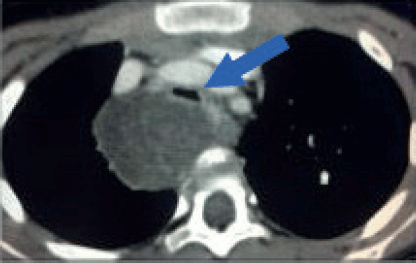

Figure 5. Tracheal compression. Contrast-enhanced axial CT image of a 6-year-old girl with a large tumour at the upper right posterior mediastinum. The lesion crosses the midline over the anterior surface of the vertebral body, at the level of the manubrium. Both, arterial and venous mediastinal great vessels are selectively enhanced with contrast. The trachea is severely compressed by the tumour (Blue arrow). This patient is at high risk of ventilatory collapse during the induction of anaesthesia.

Airway compression and cardiopulmonary function must be assessed preoperatively. Patients with clinical or radiological evidence of airway compression require pulmonary function tests (VEF1). Both pulmonary and cardiac function play a separate role in anaesthetic risk. For patients with airway compression and risk of ventilatory collapse during induction anaesthesia, it is critical to maintain spontaneous ventilation and avoid the use of muscle relaxants until the airway is secured (Figure 5). Flexible bronchoscopy may be a useful adjunct for difficult airway management or to confirm airway patency. On the other end of the spectrum, patients at high risk of cardiovascular collapse may require extracorporeal membrane oxygenation to tolerate the procedure.